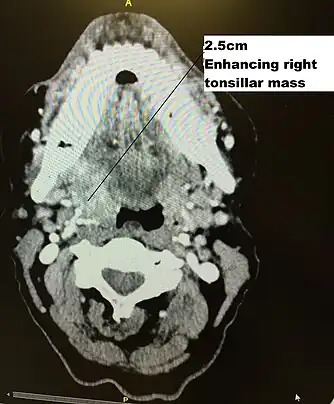

Staging is generally by the UICC/AJCC TNM (Tumour, Nodes, Metastases) system.[68] Staging is based on clinical examination, diagnostic imaging, and pathology. On imaging, involved lymph nodes may appear cystic, a characteristic of HPV+OPC.[69]

Diagram of radiation therapy contours used in treating a right tonsillar cancer

Transverse radiation contours used in treating cancer seen on above CT scan and in machine set up below